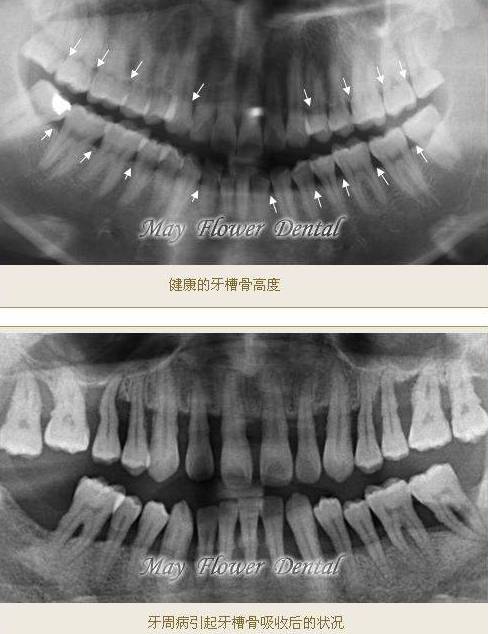

牙槽骨吸收

牙槽骨(alveolar bone)也称为牙槽突(alveolar process),是上下颌骨包围和支持牙根的部分。牙槽骨吸收是牙周炎的一个重要病理变化,由于牙槽骨的吸收,使牙齿的支持组织丧失,牙齿逐渐松动,最终脱落或拔除。牙槽骨是牙周组织中、也是全身骨骼系统中代谢和改建最活跃的部分。当人体生理情况正常时,牙槽骨的吸收与新生是平衡的,牙槽骨高度保持不变。当骨吸收增加、或骨新生减少或二者并存时,即发生骨丧失,使牙槽骨高度降低。